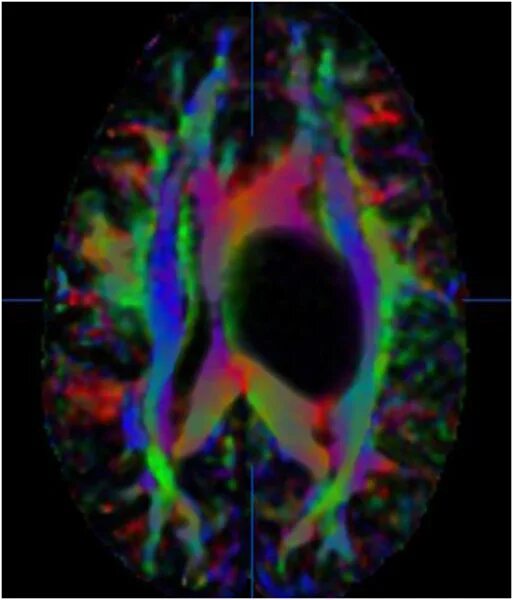

Diffusion tensor